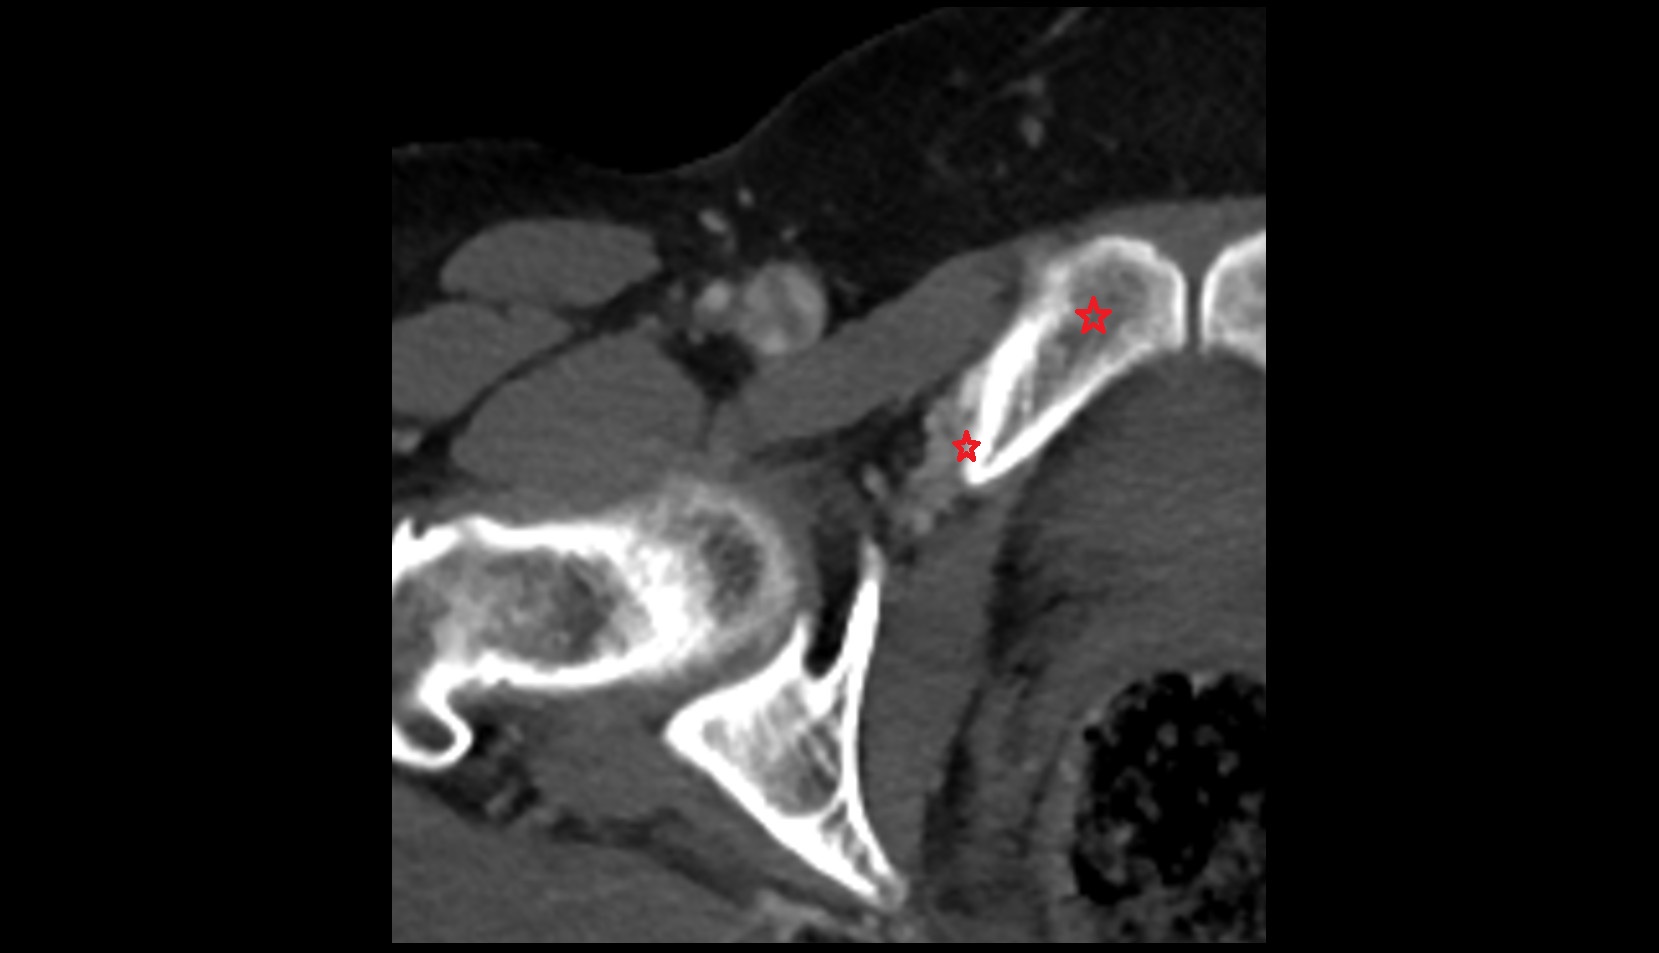

- Head of femur

- Neck of femur

- Acetabular labrum

- Articular capsule of hip joint